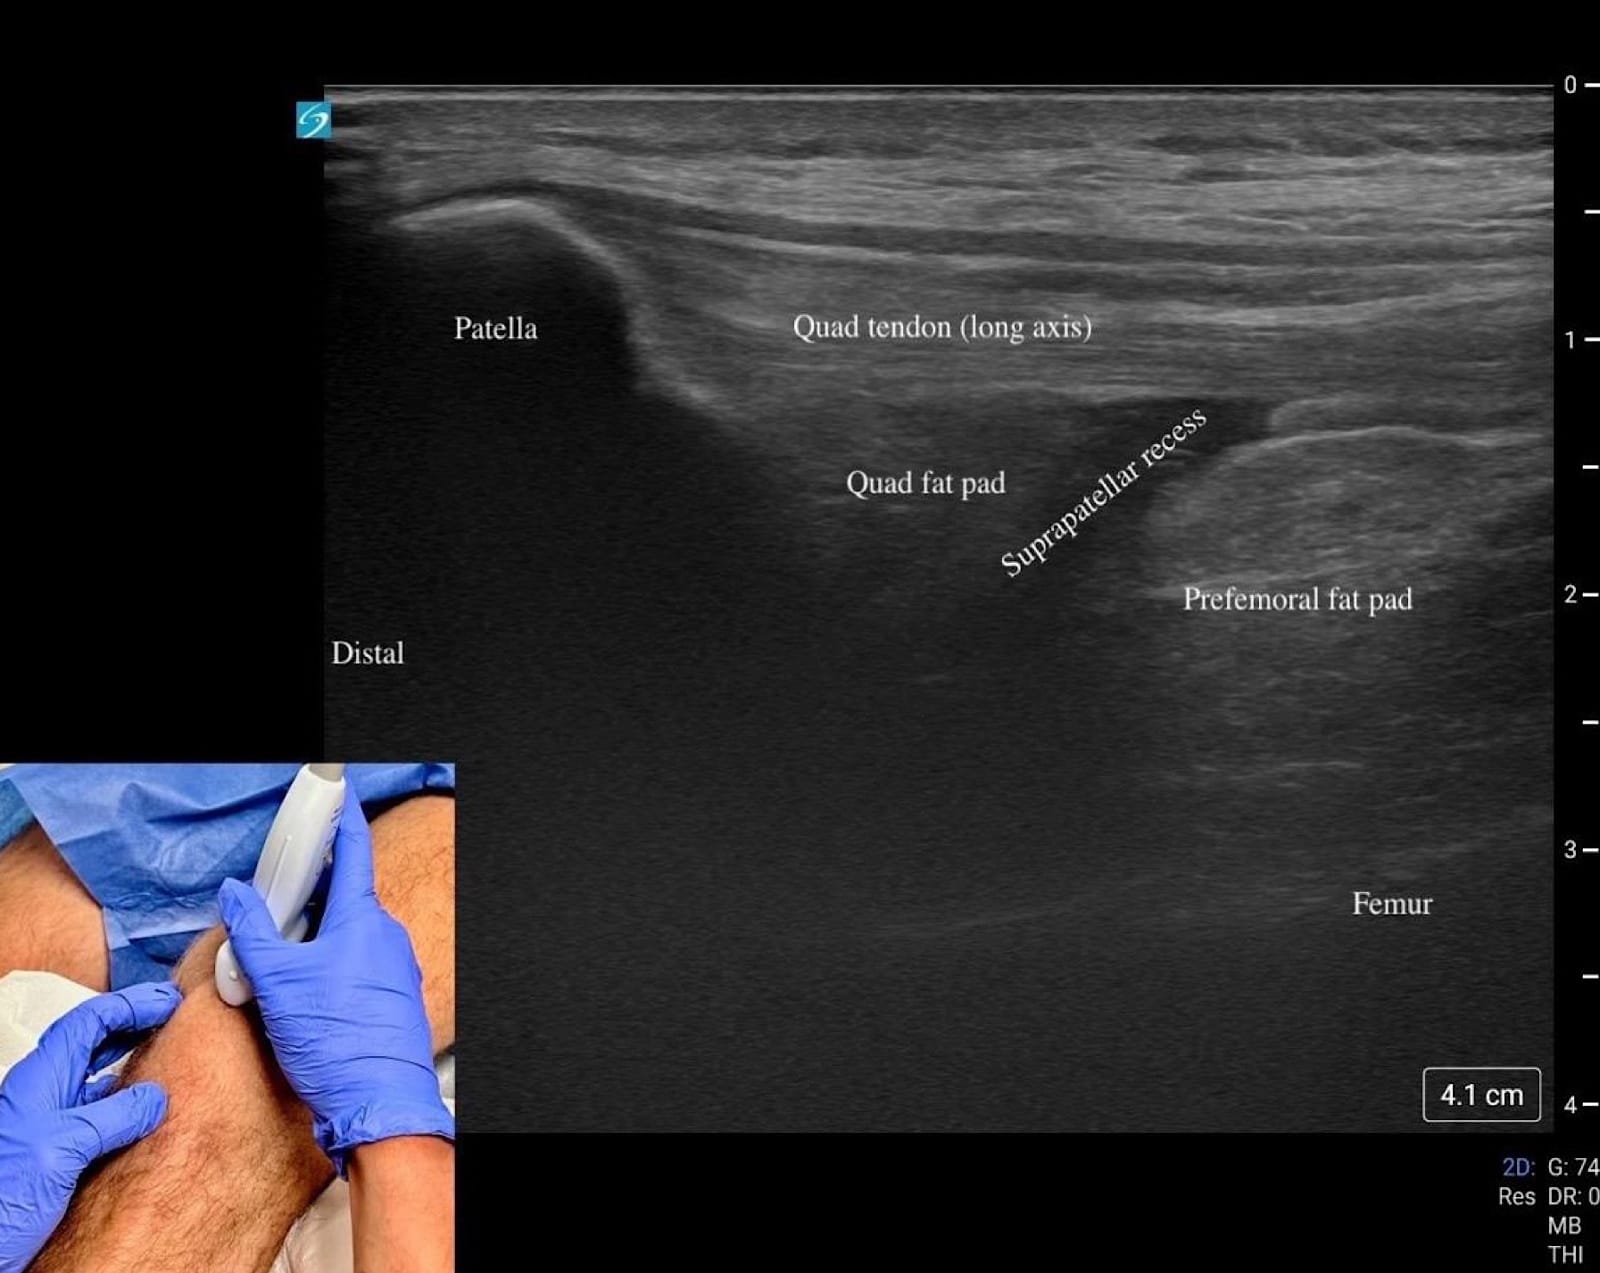

We recommend a high-frequency linear transducer (12–18 MHz). Providers can switch to a lower frequency transducer for larger body habitus or deeper structures. For anterior/medial and lateral visualization, the patient should be supine with the knee slightly flexed at 20–30° on a towel roll (Figures 1A and B, 2, and 3). For posterior, the prone position is preferred (Figure 4).

Begin by placing the transducer in short axis over the quadriceps muscle (“home base”). Rotate into long axis and scan distally over the tendon to the superior pole of the patella (Figures 1A and B).

Just beneath the tendon lies the quadriceps fat pad, followed by the suprapatellar recess, which appears as an anechoic stripe when effusion is present (Figures 5C, D).

The prefemoral fat pad above the femur provides another landmark. Continue to the patella itself in both long and short axis, assessing for cortical irregularities, fracture, or bipartite variants. Between the skin and bone lies the prepatellar bursa, a potential space for fluid that is best evaluated with minimal transducer pressure, and plenty of gel (Figure 5B).

Key Structures: Quadriceps tendon, patella, patellar tendon, suprapatellar recess (Figures 5A-D).